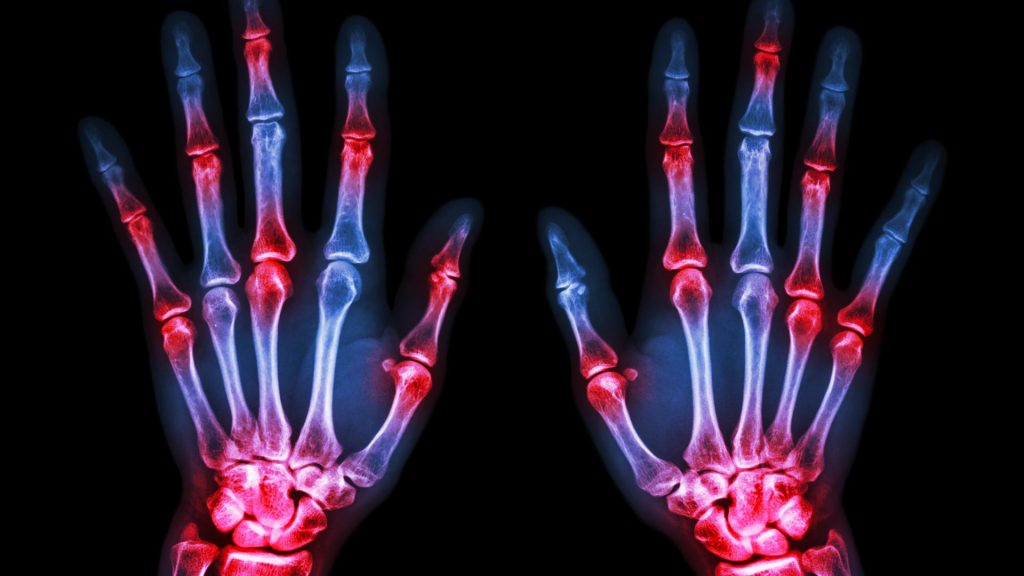

Pesquisadores da Johns Hopkins University, em Baltimore, nos Estados Unidos, relatam ter novas evidências de que uma bactéria conhecida por causar infecções inflamatórias crônicas da gengiva também desencadeia a resposta inflamatória “auto-imune” característica da artrite reumatóide (AR) crônica, que destrói as articulações. Os pesquisadores dizem que os novos achados têm implicações importantes para a prevenção e tratamento da AR.

Andrade explica que a citrulinação acontece naturalmente em todos como uma forma de regular a função das proteínas. Mas em pessoas com AR, este processo torna-se hiperativo, resultando no acúmulo anormal de proteínas citrulinadas. Isto controla a produção de anticorpos contra estas proteínas, o que cria a inflamação e ataca os próprios tecidos da pessoa, fator este que é a marca registrada da Artrite Reumatóide.

Estima-se que 1,5 milhões de pessoas em todo o país vivem com artrite reumatóide, de acordo com os Centros de Controle e Prevenção de Doenças. Os tratamentos atuais com esteróides, imunoterapia e fisioterapia ajudam alguns reduzindo ou retardando as deformidades articulares incapacitantes e dolorosas, mas não em todos os pacientes. A exploração de opções alternativas de tratamento é necessária.